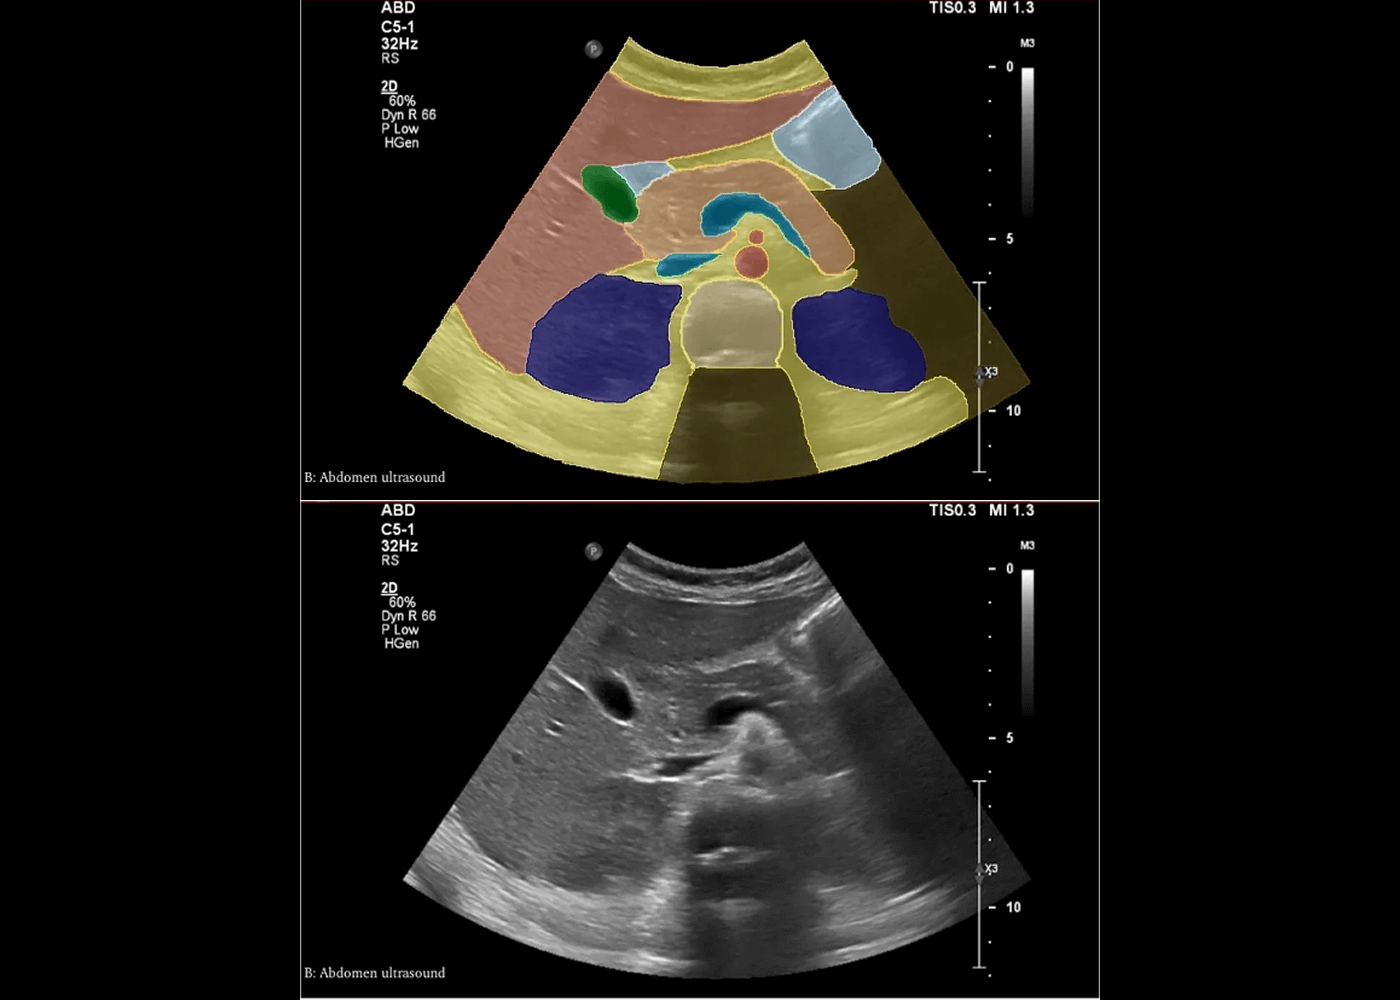

Abdomen ultrasound segmentation